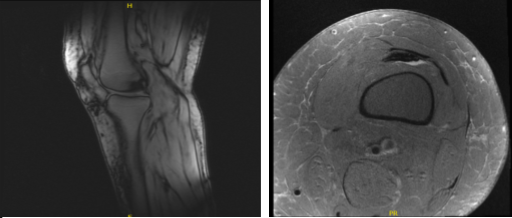

X-ray results presented and reviewed showed that there are no degenerative diseases. Advised patient to undergo MRI and found out that there is subcutaneous edema anteriorly and anteromedially.

Suspected tear in the posterior horn of the medial meniscus. There is a very faint oblique signal that appears to extend to the inferior articular surface. There is partial tear of the proximal PCL and mild chondromalacia patella and deep infrapatellar bursitis were also observed.

MRI-3T Left Knee Non-contrast